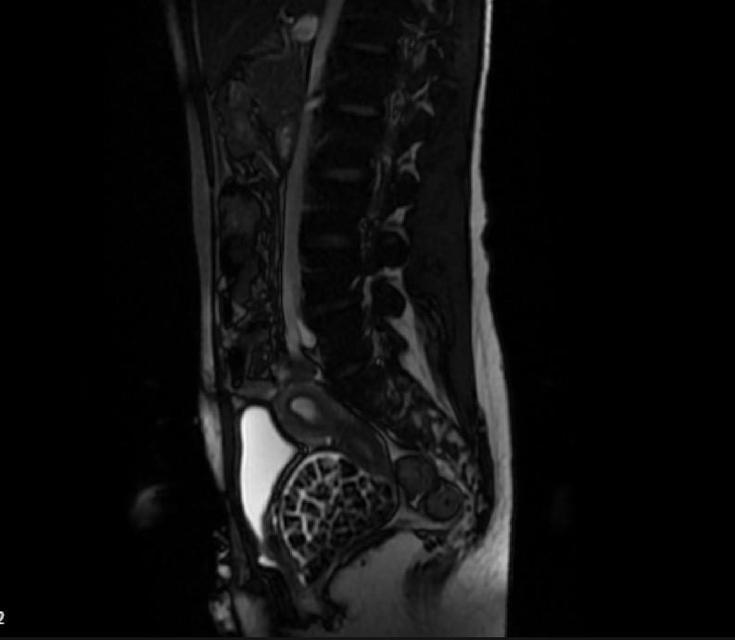

Doğumsal ürolojik hastalıkla dünyaya gelen 21 yaşındaki Fatma Nur Öztürk, şiddetli karın ağrısı şikayetiyle hastaneye gitti, yapılan operasyonla vücudundan 287 adet taş çıkarıldı. Taşlar hem sağlık ekibini hem hasta ve ailesini şok ederken uzmanlar, "Mesaneden vajene ... haberin devamı için tıklayın

VÜCUDUNDAN 287 TANE TAŞ ÇIKARILDI, DOKTORLAR BİLE ŞOK OLDU: "LİTERATÜRDE ÇOK NADİR GÖRÜLEN BİR OLAY" KARIN AĞRISIYLA DOKTORA GİTTİ, VÜCUDUNDAN 287 TANE TAŞ ÇIKARILDI UZMANLAR: "BİZ DE O KADAR TAŞ BEKLEMİYORDUK, ÇOK ŞAŞIRDIK"